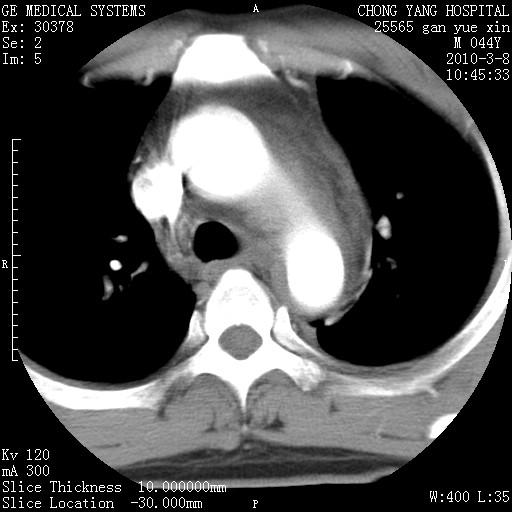

标题: CT24940:主动脉增强,典型病例。 [打印本页]

标题: CT24940:主动脉增强,典型病例。

夹层动脉瘤。

动脉夹层

夹层动脉瘤,典型

主动脉夹层。

动脉夹层的分型:

⒈debakey分型:根据主动脉夹层累及部位,分为三型:ⅰ型:原发破口位于升主动脉或主动脉弓部,夹层累及升主动脉、主动脉弓部、胸主动脉、腹主动脉大部或全部,少数可累及髂动脉。ⅱ型:原发破口位于升主动脉,夹层累及升主动脉,少数可累及部分主动脉弓。ⅲ型:原发破口位于左锁骨下动脉开口远端,根据夹层累及范围又分为ⅲa,ⅲb。ⅲa型:夹层累及胸主动脉。ⅲb型:夹层累及升主动脉、腹主动脉大部或全部。少数可累及髂动脉。

⒉stanford分型:a型:夹层累及升主动脉,无论远端范围如何。b型:夹层累及左锁骨下动脉开口以远的降主动脉。

夹层动脉瘤,少量胸水

夹层动脉瘤;左侧少量胸腔积液。

典型主动脉夹层。